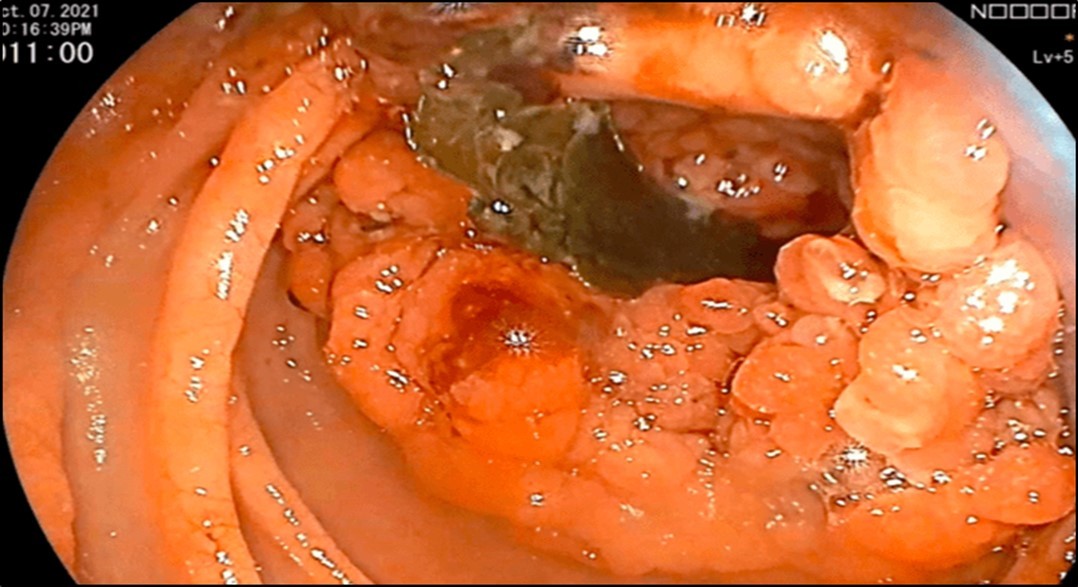

Esophagogastroduodenoscopy (EGD) revealed a fistulous opening in the third part of the duodenum and a bleeding vessel. (Figure 1) Bleeding was controlled with injection hemostasis and 3 hemoclips were deployed. The colonoscopy revealed a large obstructing, polypoid, ulcerating, and circumferential mass with areas of necrosis that was seen at the proximal transverse colon which precluded further advancement of the scope. Biopsy samples were sent for histopathology investigation and TB polymerase chain reaction (PCR) test.

Figure 1.EGD findings of a pathologic lumen and a bleeding vessel were seen at the third portion of the duodenum.

EGD findings of a pathologic lumen and a bleeding vessel were seen at the third portion of the            duodenum.

Figure 2.Colonoscopy finding of a circumferential, obstructive and nodular mass with areas of necrosis with a pathologic lumen believed to be communicating with the lumen seen on the previous EGD was seen at the proximal transverse which precluded further advancement of the scope

Colonoscopy finding of a circumferential, obstructive and nodular mass with areas of  necrosis with a pathologic lumen believed to be communicating with the lumen seen on the previous EGD was seen at the proximal transverse which precluded further advancement of the scope